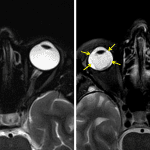

- Right retinal detachment with enhancement of the displaced membranes and of the posterior aspect of the right globe

- Retinal detachment

Right retinal detachment with enhancement of the displaced membranes and of the posterior aspect of the right globe, which though nonspecific could relate to chorioretinitis. Recommend ophthalmology evaluation.